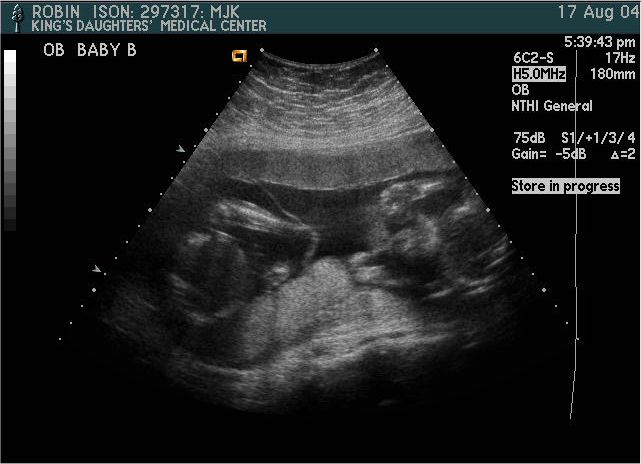

Baby B

Pictures from Ultrasound at 20 weeks.